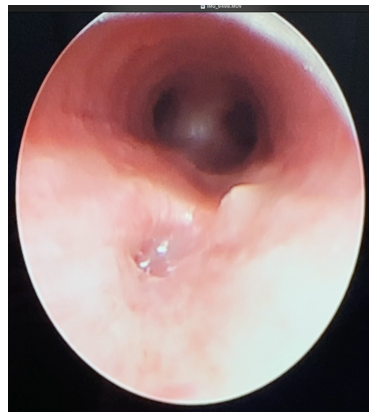

Abdominal radiographs showed persistent severe distension of the gastric chamber despite high caliber tube drainage and evidence on one occasion of bubbling of the same so tracheoesophageal fistula was suspected. Barium esophagogram was performed with evidence of complete passage into esophagus, stomach and pylorus, without a fistulous tract (Figure 1). However, due to persistent symptoms, bronchoscopy was performed to rule out congenital malformation of the airway, H-type tracheoesophageal fistula of 3 mm in diameter located 5 rings above the carina was visualized, nevertheless, endoscopic or surgical correction at this time was not possible due to hemodynamic instability (Figure 2).

Figure 1 Barium contrast esophagogram with no evidence of fistulas or extrinsic compressions. Normal.

Figure 2 Bronchoscopy: 3 mm diameter tracheoesophageal H-fistula located 5 rings above the carina.